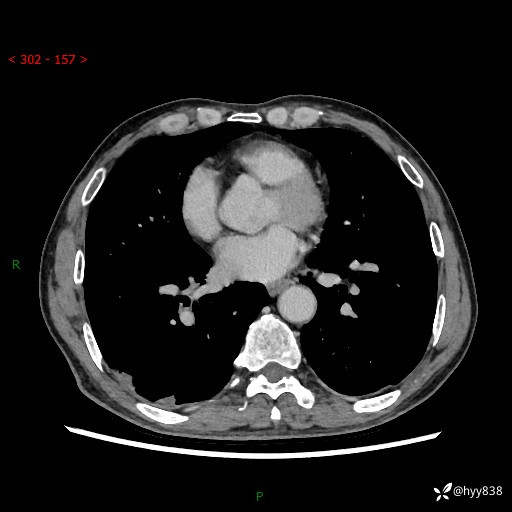

简要病史:患者3天前于我院常规体检时行胸部CT提示“右下肺结节35mm*24mm”,自觉无发热、咳嗽、咳痰,无胸痛、咯血、气促加重,无声嘶、吞咽困难,无乏力、盗汗、体重减轻等不适。为求进一步诊治,入我院求诊,门诊以“右下肺结节待查”收入我科。患者3天前于我院常规体检时行胸部CT提示“右下肺结节35mm*24mm”,自觉无发热、咳嗽、咳痰,无胸痛、咯血、气促加重,无声嘶、吞咽困难,无乏力、盗汗、体重减轻等不适。为求进一步诊治,入我院求诊,门诊以“右下肺结节待查”收入我科。 起病以来,患者精神、食欲、睡眠可,体力稍差,大小便正常,体重无明显变化。

辅助检查:CT

增强